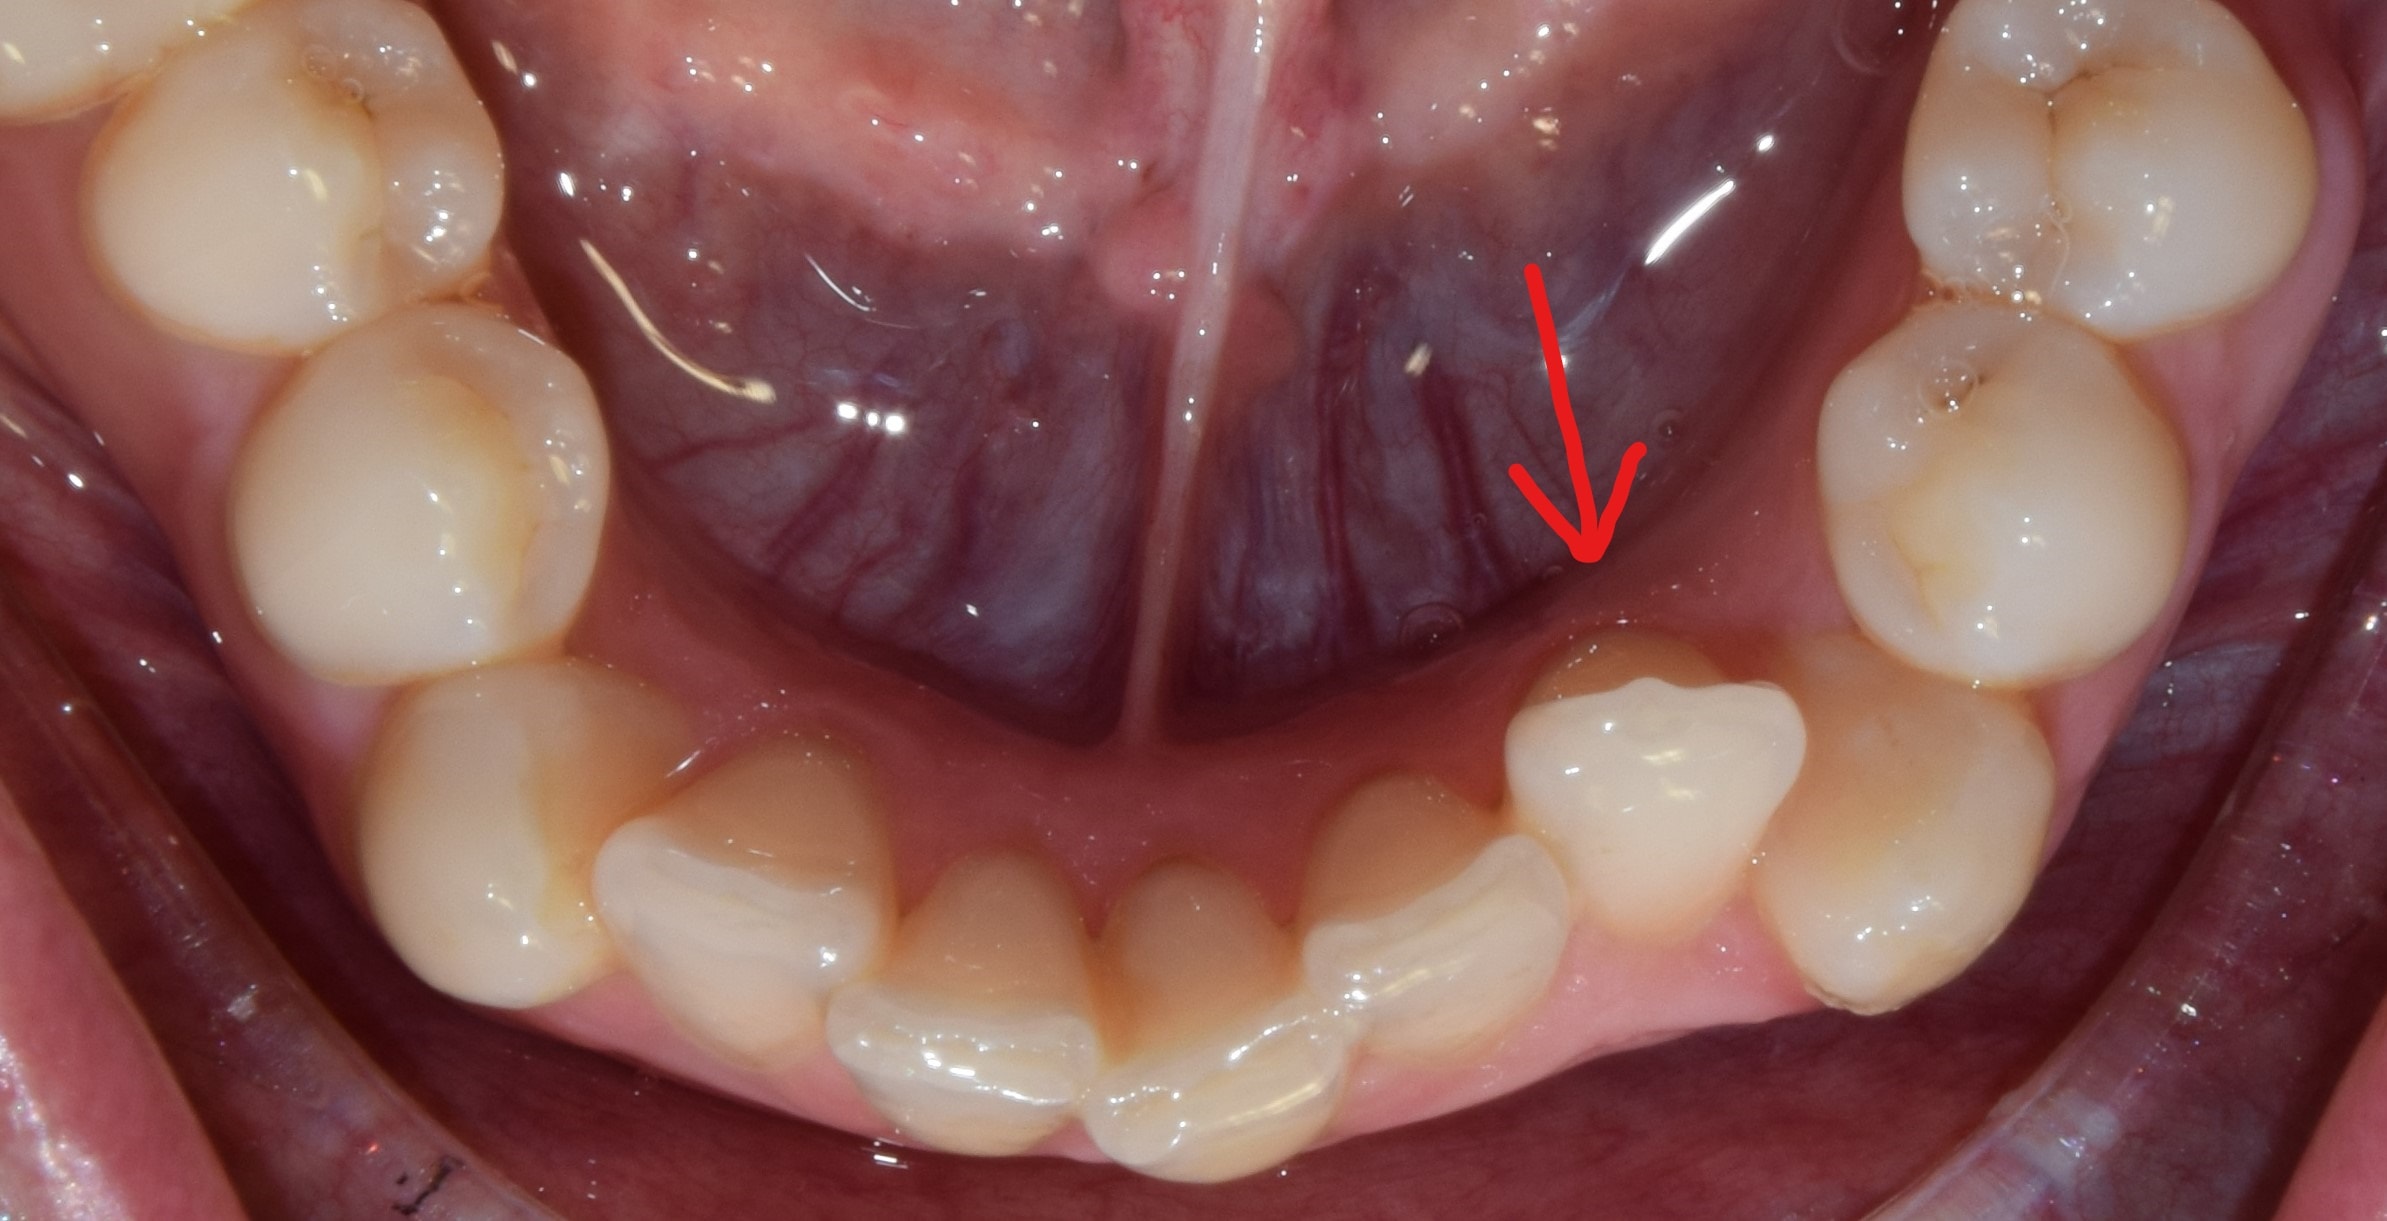

Ajakfék

Az ajakfék nem más, mint az ajkak mozgását szabályozó, korlátozó nyálkahártya tömörülés, mely az alsó és felső első metszők fölött-között helyezkedik el. A túlságosan kifejezett ajakfék beszédproblémát, ínyvisszahúzódást, vagy akár rést is okozhat a metszőfogak között. A köteges, kifejezett ajakféket egy kis szájsebészeti beavatkozás során korrigálni lehet, legkíméletesebben lézerrel.